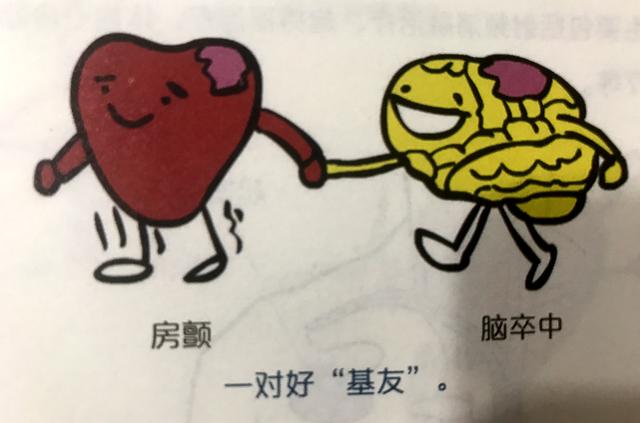

脳梗塞の原因としては、よく耳にする心房細動もあるが、心房内に塞栓ができると、それが外れて脳梗塞になることがある。したがって、心房細動も脳梗塞の重要な原因である。もちろん、心房細動による脳梗塞と脳動脈硬化症や脳血栓症による脳梗塞とは病態基盤が全く異なるので、通常の治療法も異なり、抗血小板療法を強化する場合と、抗凝固療法に注意する場合とがある。

4、一目で答えの比較は、ここで少し拡大するように、脳塞栓症は、多くの場合、心機能の問題を伴っている、臨床我々は、脳塞栓症患者は、多くの場合、心房細動を伴うことがわかった、この異常な心拍パターンは、多くの場合、脳塞栓症をもたらす脳に到達する体の血液循環で、血栓オフの心臓の壁に取り付けられている。

5、心房細動患者に対して、我々は積極的に心房細動による害を予防しなければならない、心房細動患者の脳血管リスクは普通の人より約60%高い、どのように心房細動に介入するか、古い治療方法であるワルファリン薬の使用(弊害は出血のリスクが増加することで、定期的に病院に行って凝固機能を見直す)、現在では新しいタイプの抗凝固薬(例えば:ダビガトランやリバロキサバンドロン薬)を使用する傾向があり、安全性ははるかに優れています。現在では、より安全性の高い新しい抗凝固薬(例えば、ダビガトランやリバロキサバンドロン)が使用されることが多くなっています。

脳塞栓症を心臓性脳塞栓症と呼ぶ人もいるが、これは脳塞栓症の一般的な原因が心臓にあり、心臓の異常病変が塞栓を生じやすいことを示している。心房細動、リウマチ性心疾患、急性心筋梗塞、人工心臓弁などである。

大別すると、脳梗塞の原因となる血栓には、プラークが破裂して血栓を形成する動脈硬化が大部分を占める場合と、心筋梗塞の不整脈である心房細動によって形成される血栓の2種類がある。

また、不整脈の心房細動によってできる血栓もある。正常な心臓では、拍動のたびに心臓内の血液がすべて送り出され、心臓内に血液が残留することはない。しかし、心房細動が起こると、血流の一部が心臓内に滞留し、血液が長時間滞留すると、血液が固まって血栓(血の塊)を形成する。そして、この血栓が血管とともに脳血管に流れ込み、脳血管を閉塞して脳梗塞を引き起こす。このような脳梗塞を防ぐには、心房細動が発見されたら、抗凝固療法、心房細動を治す手術、左耳の閉塞など、どのようなものであっても、専門医を見つけ、専門的な治療を受け、正式に治療することである。